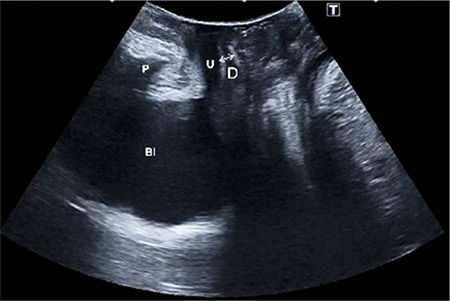

Material and methods: Continent patients who had undergone TOT surgery for SUI were eligible. Objective treatment for SUI was defined as the absence of urine leakage during a stress test. Translabial perineal ultrasound was performed six months after surgery. The successful surgical group was split into two subgroups based on the distance from the posterior of the urethra at the bladder neck to the nearest proximal edge of the tape: <5 mm and >5 mm. In addition to these, band percentile, the descent of bladder neck and urethra length measured by perineal ultrasound, pubo-urethral distance, urethral thickness, detrusor thickness, cystocele descent, rectal descent, and uterine descent were evaluated. Preoperative and postoperative results of the standardized and internationally valid incontinence questionnaires Incontinence Questionnaire Urinary Incontinence Short Form and Female Sexual Function Index (FSFI) were compared between groups.

Results: Eighty-two patients were included. The postoperative FSFI scores for the >5 mm group were significantly lower than those of the <5 mm group, including the postoperative FSFI average, all subscales except lubrication, and average change scores due to the operation (p<0.001). There was no statistically significant relationship between the percentile occupied and postoperative FSFI score (p=0.553), and the FSFI preoperative-postoperative difference was not significant (p=0.905).

Conclusion: Sexual functions are more affected in patients with a mesh-urethra distance >5 mm as measured by perineal ultrasound.